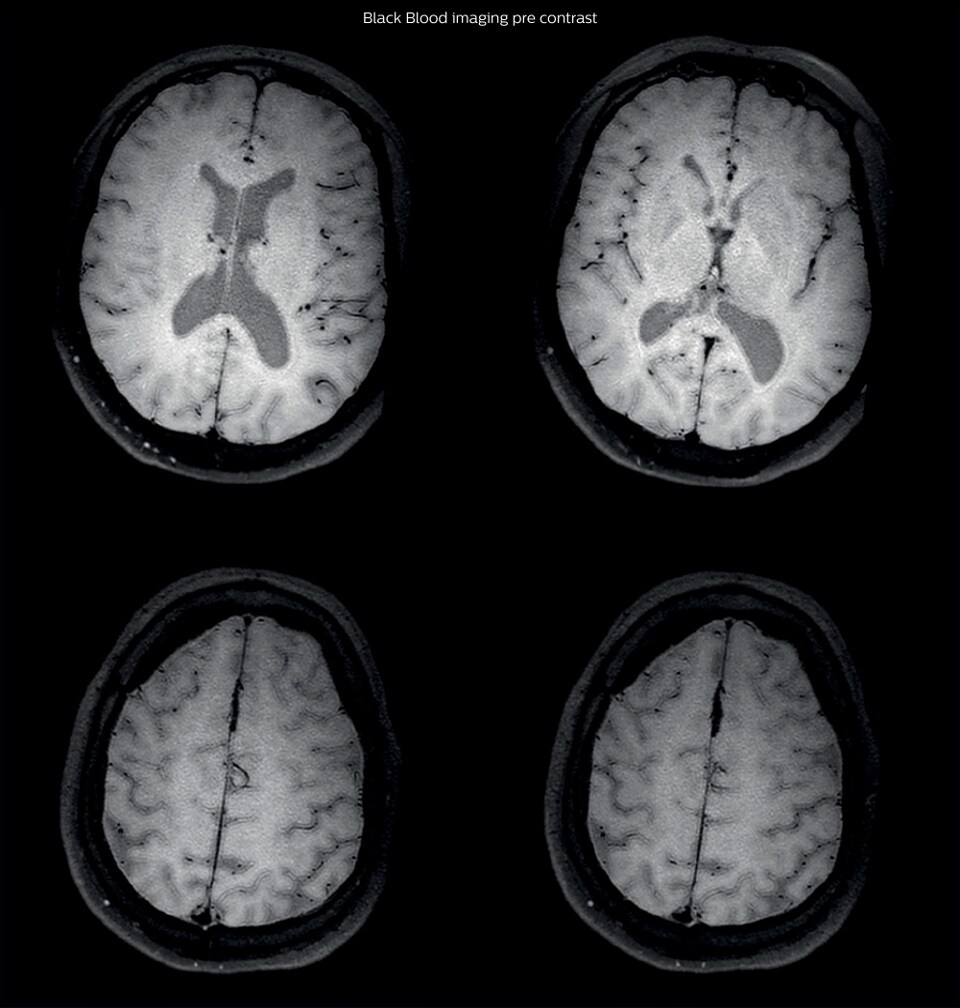

After a conventional routine MR imaging examination, the suspicion of vasculitis arose, therefore we performed an MRI including Black Blood imaging in a separate session. The dedicated ExamCard includes diffusion, FLAIR, MR angiography using TOF, and 3D T1 MRA with bolus injection. This ExamCard also includes Black Blood imaging before and after contrast. This examination was performed on our Ingenia 3.0T. Black Blood scan time 4:39 min, acquired voxel size 0.75 x 0.75 x 1.0 mm, 21 slices.

On FLAIR images we can see some nonspecific high signal abnormalities in frontal white matter bilaterally. On DWI we can see acute ischemic lesions which appear with high signal intensity. Arrows show vessel wall enhancement which appears concentric and homogeneous in different cerebral territories.

After one month of treatment, post-contrast Black Blood images at the exact same levels as in the figure above show disappearance of the vessel wall enhancements which were seen on the previous examination.